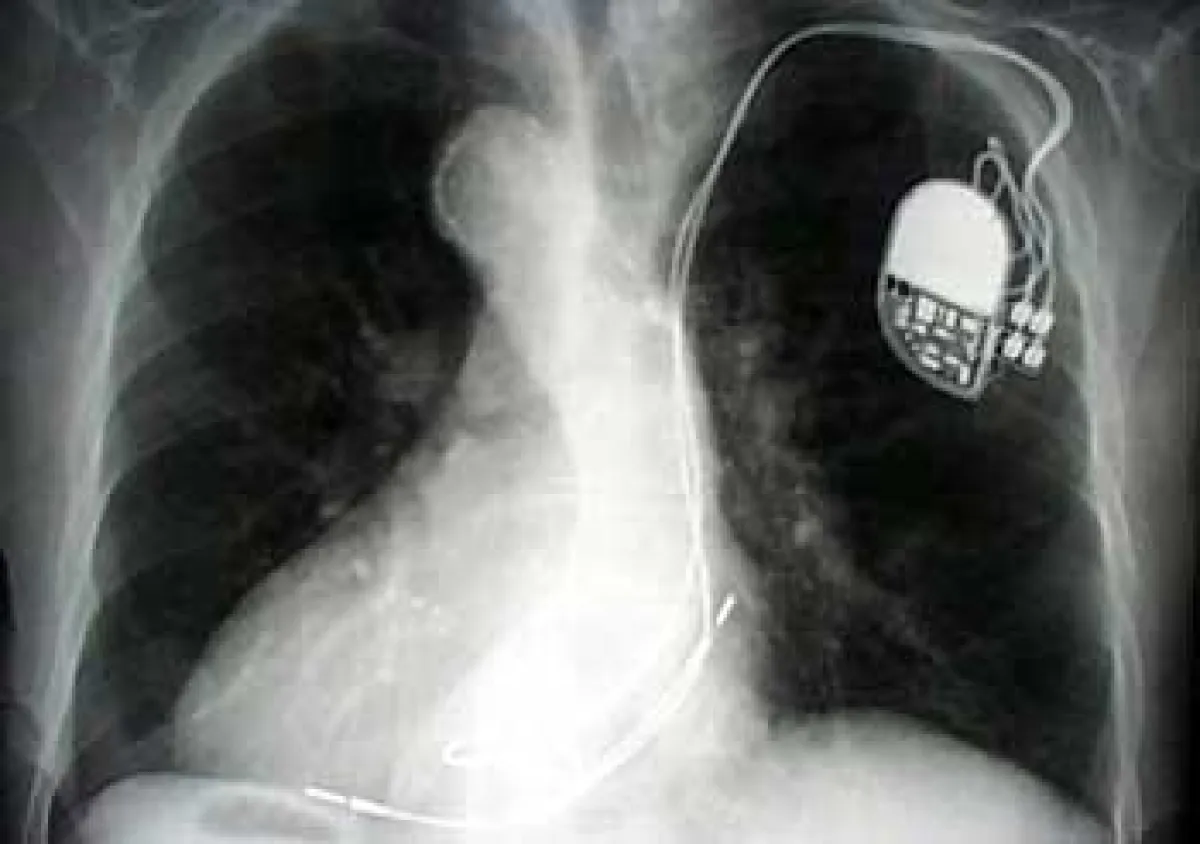

Ein Herzschrittmacher ist ein Gerät, das in regelmäßiger Abfolge einen elektrischen Impuls abgibt. Dieses Gerät wird von einer Batterie betrieben, die mit dem Steuerungssystem fest verbunden ist und nicht gesondert ausgewechselt werden kann. Die Geräte sind im Laufe der technischen Entwicklung immer kleiner geworden und haben inzwischen die Größe eines Streichholzbriefchens erreicht.

Dennoch kann der Schrittmacher nicht direkt in das Herz eingesetzt werden. Vielmehr wird er unterhalb des Schlüsselbeins unter die Haut oder unter einen Muskel eingebracht und der elektrische Impuls über extrem bewegliche Kabelsysteme, die Schrittmachersonden, dort hingeleitet, wo die Taktgebung das Leitungssystem des Herzens erreichen soll. Die Sonden werden über Blutgefäße direkt in die rechten Herzhöhlen geführt.

Moderne Schrittmachersysteme können sowohl die Herzvorhofebene als auch die Hauptkammerebene getrennt mit Impulsen versorgen. Das erlaubt eine individuelle Anpassung des Zusammenspiels der Herzkammern, da diese Schrittmacher von außen, d. h. auch nach der Anlage des Schrittmachers, durch die intakte Haut eingestellt, “programmiert” werden können.